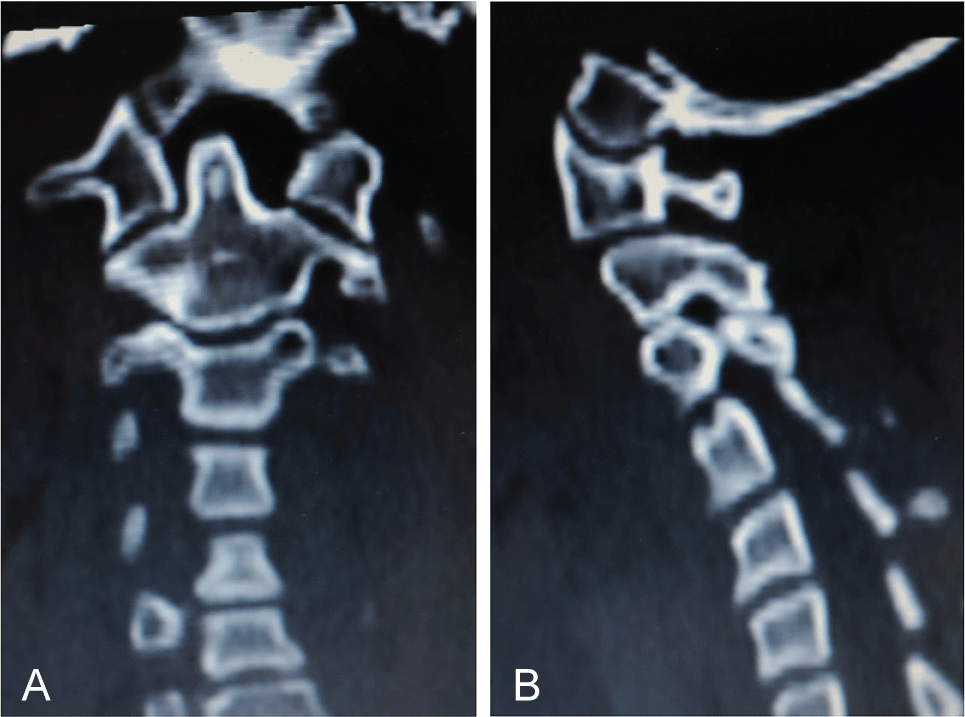

This patient study was approved by the Ethics Committee and was conducted following completion of the corresponding informed consent. A 10-year-old male patient in 2008 had consulted for a torticollis deformity that had originated during early childhood. This delay in first diagnosis is because patient is inmigrant and without diagnosis or previous treatment. Patient had classical deformities of torticollis: Shortening of SCM muscle, lateral inclination of the neck, smaller and higher eye, contralateral torsion with chin rising. Moreover, the patient also presented with a left-side facial deformity. The patient was not referred for any traumatic or infectious etiology of the oropharynx or for digestive or renal diseases. It was made a wide differential diagnosis, especially for to exclude nonmuscular causes of torticollis, presents in 18% of patients [1], Klippel-Feil anomalies (30%), posterior fossa tumors, syringomyelia or Arnold-Chiari malformation (51%) [1,2]. Additionally, neurologic exploration was done by a pediatric neurologist. Problems like dystonia, ataxia or abnormal deep tendon reflexes in upper and lower limbs did not exist. Also, osteocongenital neurological pathologies of the spinal cord and brain tumor were excluded by a pediatric neurologist. After these exclusions were made, we confirmed a diagnosis of inveterate congenital muscular torticollis. Preoperative studies, radiographic imaging, Computed Axial Tomography (CT) scans and Magnetic Resonance Imaging (MRI) of the cervical spine and skull (Figure1a, Figure 1b, Figure 2a, Figure 2b, Figure 3a, Figure 3b, Figure 4a, Figure 4b) highlighted Klippel-Feil Syndrome, fusion defects of the vertebral arches of the atlas, diastematomyelia and hypoplasia of the occipital condyles. CT images demonstrated, deformity of the anterior arch of the atlas was observed, consisting of hypoplasia of the right half and deformity and hypoplasia of the posterior arches C1 and C2 with concavity of the right posterior hemi-arch and convexity of the left arch, causing asymmetry of the spinal canal. Additionally, subluxation of the odontoid apophysis toward a right lateral mass of the atlas was observed (Figure 2a, Figure 3a). MRI showed deformity with extreme narrowing of the odontoid apophysis and irregular formation of the spinal canal with displacement of the spinal cord in the direction of the concavity of the torticollis (Figure 4a, Figure 4b). In 2009, unipolar distal tenotomy of the left SCM was performed, followed by orthotics and rehabilitation with notable improvement in cervical mobility but with minimal effect on facial asymmetry. In the 5-year postoperative CT and MRI, there were no significant changes in preoperative vertebral bone deformities, either visually or through the morphology of the spinal canal (Figure 5a, Figure 5b, and Figure 6).

Figure 2: CT: a) Odontoid apophysis asymmetry and right anterior vertebral hemi-arch hypoplasia; b) Spinal canal asymmetry of vertebral posterior arches: Flattening on the right side and convexity on the left. View Figure 2

Figure 3: 2D CT: a) A coronal plane search found odontoid apophysis symmetry regarding lateral masses of the atlas; b) A sagittal plane search found an occipital condyle of normal morphology. View Figure 3

Figure 5: a) Postoperative CT (5 years follow-up); b) Persistent abnormal positions of odontoid apophysis and asymmetry of the posterior vertebral arches and cervical spinal canal. View Figure 5